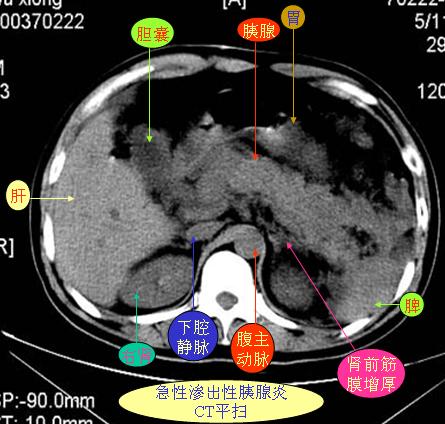

腹部ct解剖与基本病变